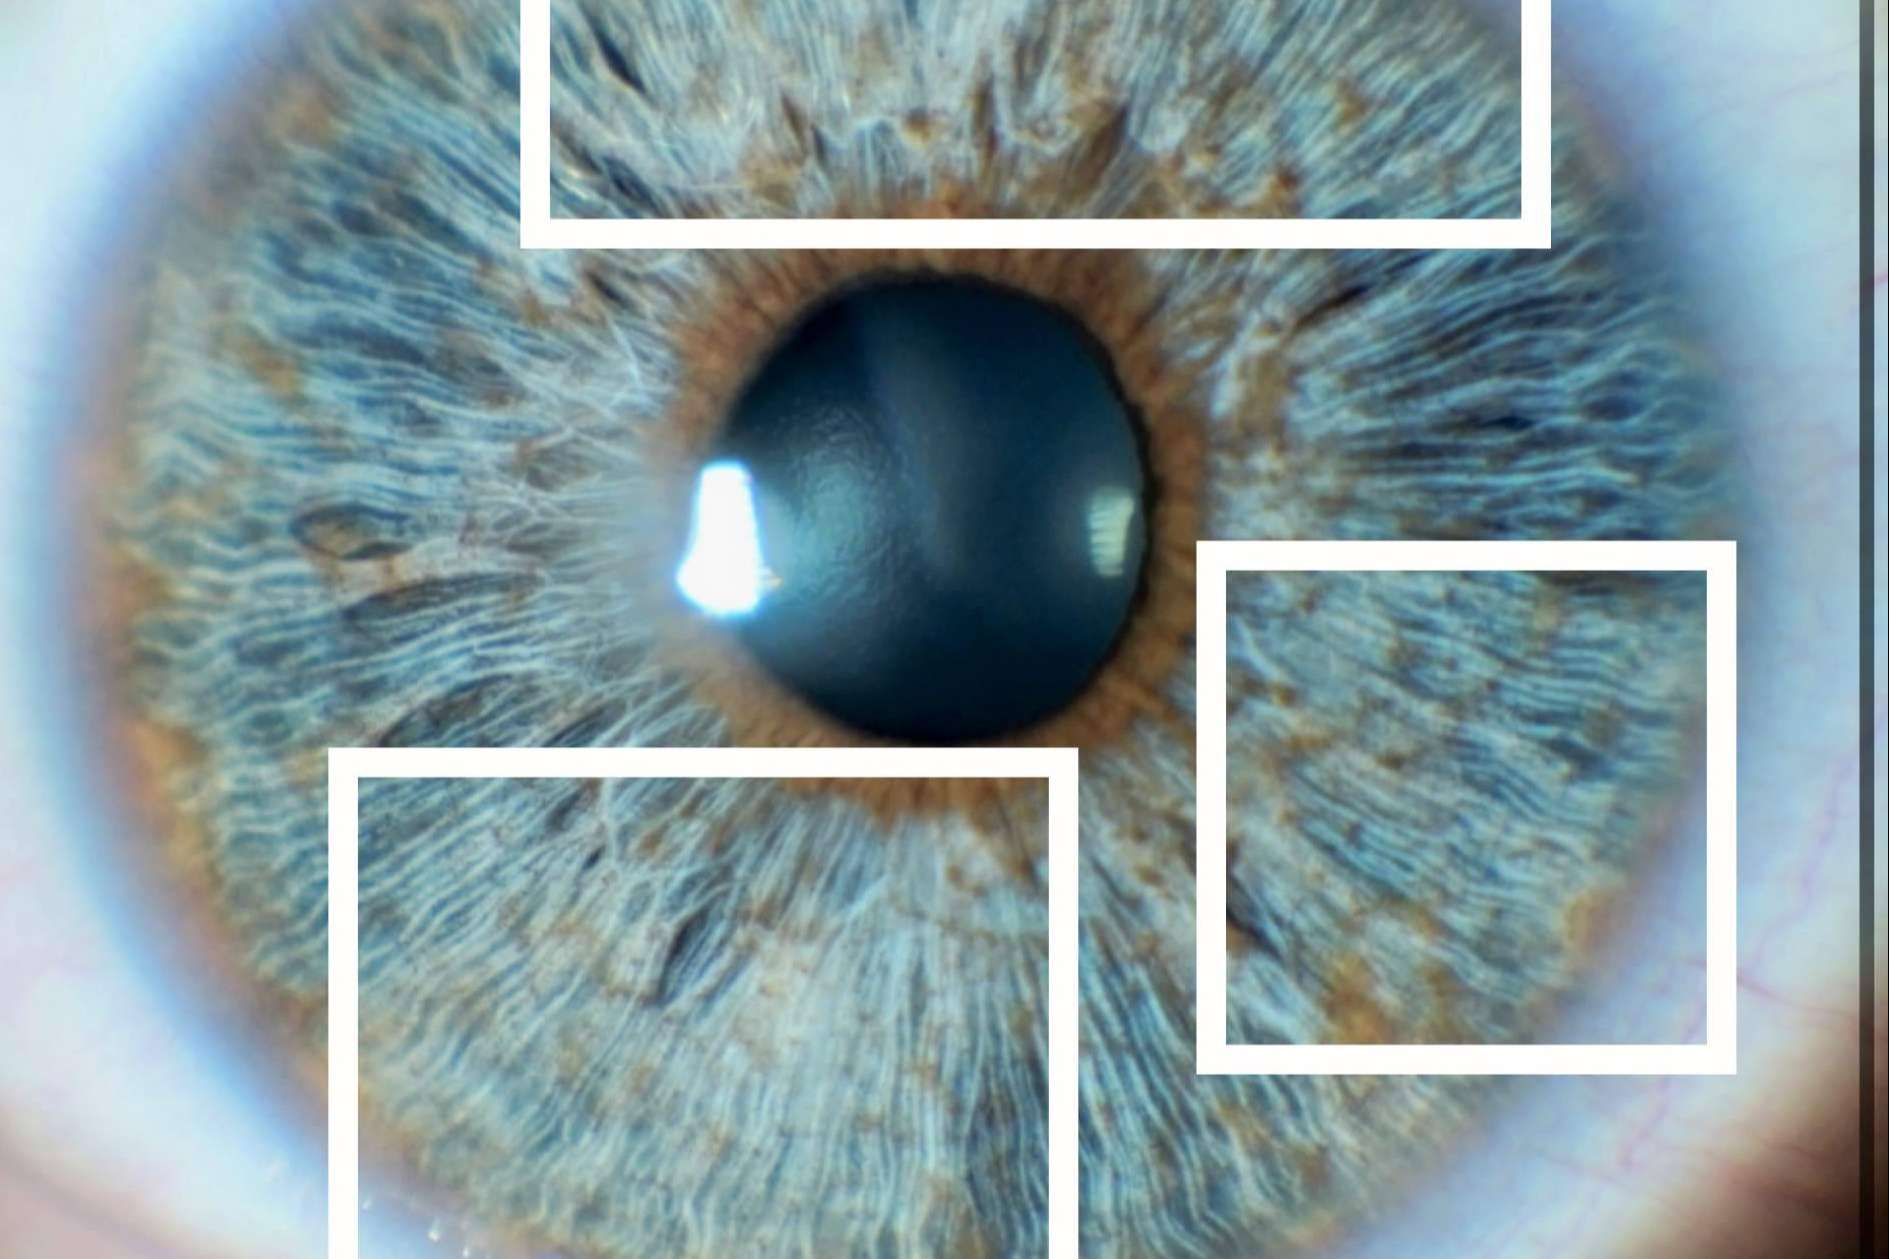

Para ilustrar este concepto, se han incluido imágenes que ejemplifican la diferencia entre un iris con zonas opacas (indicando una menor densidad de colágeno) y un iris con zonas brillantes (indicando una mayor densidad de colágeno). Estas imágenes proporcionan una representación visual de cómo el colágeno puede afectar la apariencia del iris después del tratamiento.